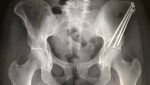

My x-rays looked great. He was really impressed with my progress, recovery and bone growth. So much so that he said I could get my screws out a month early! I was speechless and shocked and then so excited! I really did not expect that. I set a date for March 22nd, so the next time I see him will be for my pre-op appointment for the hardware removal. I’m so ready to have all this behind me!